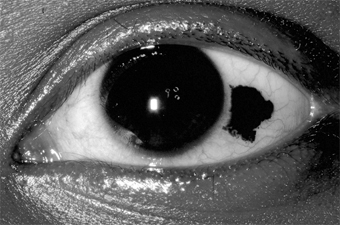

Nevus (Figure 5-26)

One-third of melanocytic nevi of the conjunctiva lack pigment. Over half have cystic epithelial inclusions that can be seen clinically.

Figure 5-26

Figure 5-26: Conjunctival nevus. Note sharp borders.

Histologically, conjunctival nevi are composed of nests or sheets of nevus cells. Conjunctival nevi, like other nevi, rarely become malignant. Many are excised because they are disfiguring.

Pigmented conjunctival nevi must be distinguished from primary acquired melanosis of the conjunctiva. The latter occurs later in life (after the third decade), is usually unilateral, tends to wax and wane in degree of pigmentation, and, depending on the degree of cellular atypia, has a risk of becoming malignant ranging from nil to 90%.